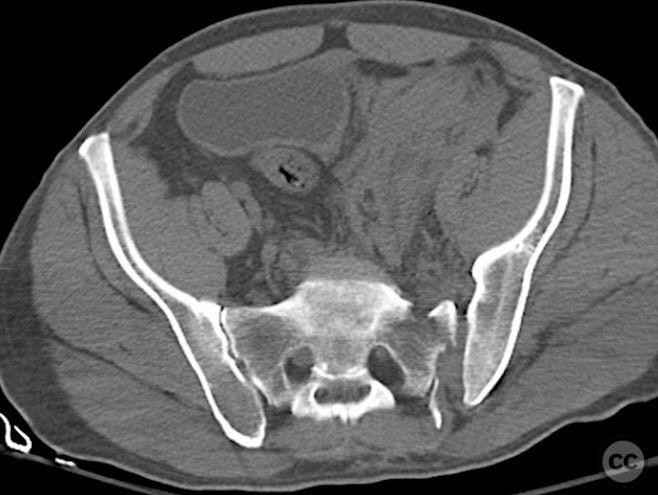

Clinical and radiological findings:  Middle-aged male involved in a motor vehicle accident sustained a complete symphysis pubis (SP) disruption and left sacroiliac (SI)/sacral combination fracture-dislocation (AO/OTA 61-C1.3). The patient presented with an open traumatic posterior pelvic wound. Initial assessment revealed hemodynamic instability requiring urgent laparotomy and subsequent angioembolization for pelvic hemorrhage. Axial CT imaging demonstrated significant displacement of the anterior and posterior pelvic ring, with embolic coils visible post-intervention.

Planning remarks:  The preoperative plan included staged fixation: initial supine positioning for low midline exposure and open reduction internal fixation (ORIF) of the pubic symphysis, followed by prone repositioning for irrigation and debridement (I&D) of the open posterior wound and stabilization of the posterior pelvic ring via iliosacral screw fixation under fluoroscopic guidance.